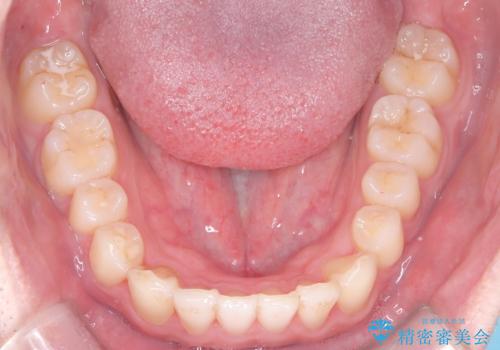

- 前歯が出ていることを主訴に来院されました。

歯列の幅が狭かったため、横に広げながらスペースを作り、叢生の改善を行いました。

左側の犬歯関係も治療前より良い状態で治療を完了することができました。

今回は臼歯部の遠心移動を行うために2級ゴムを使用しています。